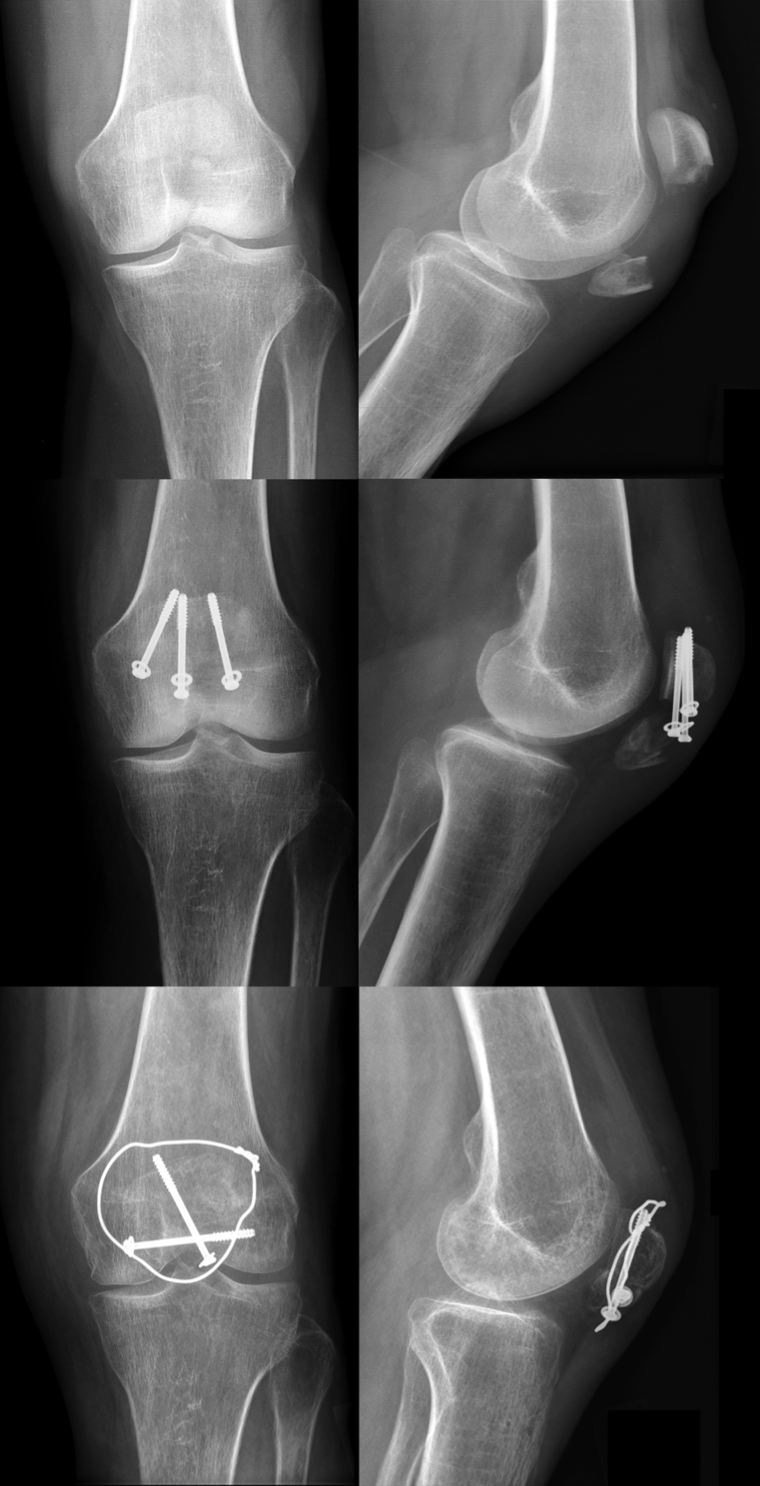

As previously mentioned, every unstable fracture of the patella requires operative intervention. The modified tension band wiring, according to AO principles, is the most accepted and widely used technique for the treatment of displaced fractures of the patella, although several other techniques involving combinations of fixation techniques (i.e. K-wires, screws and cerclage wiring; Figure 3 [Fig. 3]) have been published [8], [60]. From a biomechanical point of view, the surgical procedure aims to neutralize tension forces applied to the patella via the extensor mechanism and convert them into compression forces. For this purpose, at least two K-wires are placed perpendicular to the fracture line and a tension band is applied in an eight-shaped manner to secure reduction. The ends of the K-wires are then twisted and buried in the patella.

Figure 3: Preoperative X-rays of a comminuted patella fracture (above). 3 months post-surgery using a combination out of K-wires, screws, and an eight-shaped cerclage wiring (below).

Screw fixation may decrease the risk of fragment dislocation as a result of tension band laxity and serves as a longitudinal stabilization of the fracture (Figure 4 [Fig. 4]). Screws should be applied perpendicular to the fracture line and fit the size of patellar bone (e.g. 3.5 mm cortical screws).

Figure 4: Preoperative X-rays of a comminuted patella fracture (above). 3 months post-surgery using screw fixation and modified tension band (below).

Loss of reduction

Loss of reduction occurs in up to 20% of operatively treated patellar fractures (Figure 6 [Fig. 6]) [9], [10], [63], [76]. This is usually attributed to technical errors, most commonly involving improper placement or tensioning of the modified tension band, consecutively causing construct instability and fracture displacement [37], [76].

Figure 6: Preoperative X-rays of a transverse patella fracture (above). Loss of reduction with screw pullout 3 month after surgery (middle). 3 months after revision surgery with screw fixation and additional modified tension band (below).

Miller et al. were able to show that the use of K-wires with or without tension band correlates with higher failure rates, compared with the use of screws [58]. The indication for revision surgery is given if the fragments separate more than 3 mm from each other or if the articular surface presents with an incongruity of more than 2 mm [10].